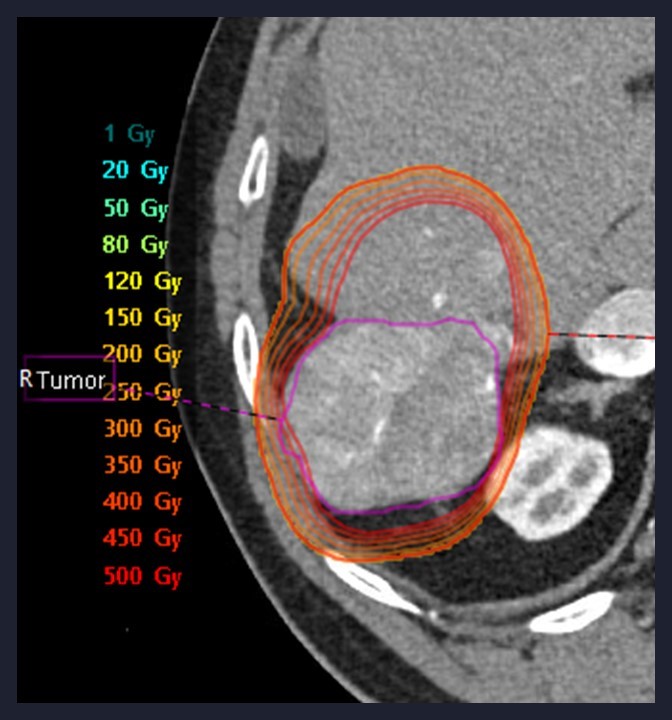

Dr. Berman’s academic and clinical career is distinguished by a strong commitment to innovation in minimally invasive cancer therapy. He has played pivotal roles in numerous clinical trials investigating emerging locoregional and immuno-oncology strategies, including investigator positions in the CapTemY90 trial and other advanced-phase studies for neuroendocrine tumors, HCC, and pancreatic cancer. He has authored over 30 peer-reviewed publications and book chapters, including work on Y-90 dosimetry, intraoperative embolization, and imaging response assessment, and has been recognized with honors such as “Top Doctor” in San Diego Magazine and the UCSD Resident Teaching Award.

A respected voice in the field, Dr. Berman has delivered over 60 invited lectures nationally and internationally, including at major conferences such as the Society of Interventional Oncology (SIO), Society of Interventional Radiology (SIR), and Western Angiographic Society. He has led sessions on personalized Y90 dosimetry, tumor ablation, and strategies for combining local therapies with systemic treatments. His educational leadership is evident through his involvement in SIR’s Residency Essentials Council, the SIO Education Committee, and as a site mentor for students and residents.